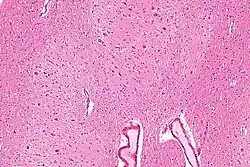

The dentate nucleus refer to a pair of deep cerebellar nuclei deep within the white matter of the cerebellum of the brain with a dentate – tooth-like or serrated – edge. The dentate forms the largest pathway between the cerebellum and the remainder of the brain.[1] It is the largest and most lateral of the four pairs of deep cerebellar nuclei, the others being the globose and emboliform nuclei, which together are referred to as the interposed nucleus, and the fastigial nucleus.

The dentate nucleus is highly convoluted, with gyri (ridges on the cerebral cortex) and sulci (furrows or grooves on the cerebral cortex). Its formation is coincident with a critical period of extensive growth in the fetal dentate. The dentate nucleus becomes visible in the cerebellar white matter as early as 11–12 weeks of gestation, containing only smooth lateral (towards the side(s) or away from the midline) and medial (towards the midline) surfaces. During this time, the neurons of the dentate nucleus are similar in shape and form, being mainly bipolar cells.[2]

Morphology